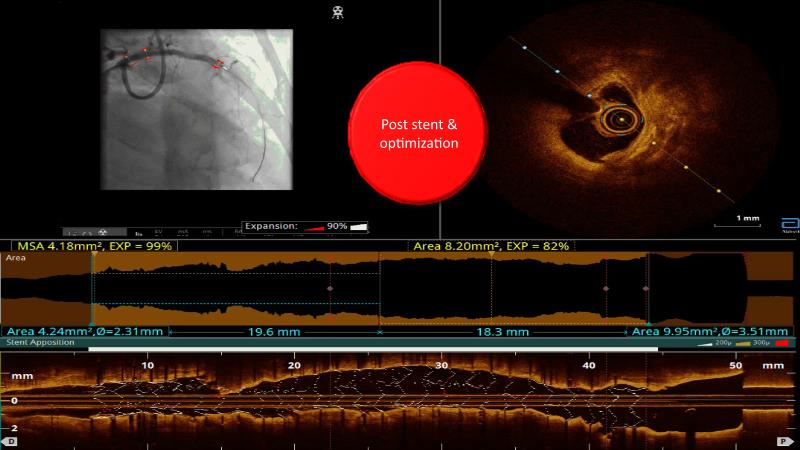

Watch this case-in-point presentation focusing on decision-making in complex PCI using OCT plus AI to understand how to take the right measurement throughout the procedure, how artificial intelligence aids in decision making during imaging-guided PCI, and to gain skills in interpreting OCT imaging, among others!

- To gain skill on OCT imaging interpretation

- To know what OCT images are actionable and how to decide

- To understand how to take the right measurement across the entire procedure

- To learn how artificial intelligence works in support of decision making during imaging-guided PCI